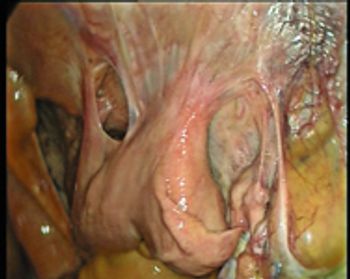

Uteropexy can help mares that develop post-mating endometritis.